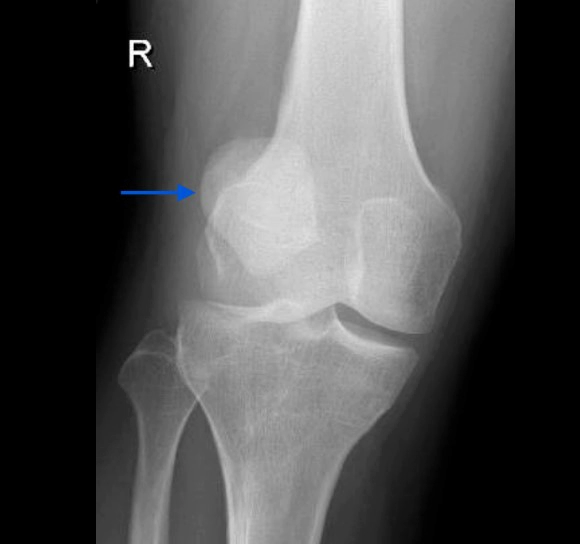

가장 심각한 슬개골 탈구의 증상 중 하나는 무릎의 가시적인 변형일 수 있습니다. 슬개골이 원래 위치에서 크게 이동한 경우, 무릎의 형태나 구조가 훼손되어 보일 수 있습니다. 이는 무릎 뒷부분이 비정상적으로 부풀어 오르거나, 무릎이 정상적인 위치보다 앞으로 또는 뒤로 늘어나 보이는 형태로 나타날 수 있습니다.